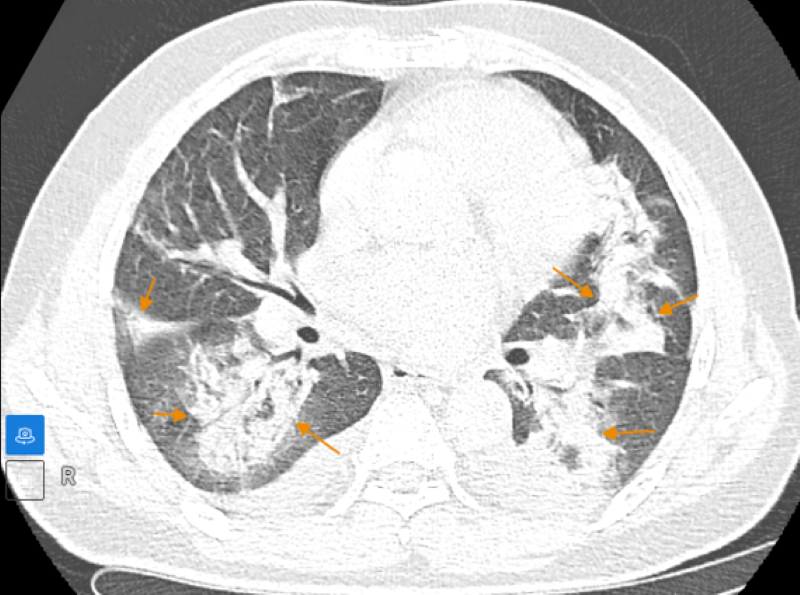

Trước tiên, người bệnh cần tìm đến cơ sở y tế uy tín để kiểm tra, chẩn đoán chính xác tình trạng bệnh lý. Một số phương pháp chẩn đoán tình trạng xoang sàng sau mũi bị viêm là nội soi mũi, cấy hút dịch xoang, chụp X - quang và thực hiện một số xét nghiệm khác xét nghiệm dị ứng, miễn dịch,… Sau khi có chẩn đoán chính xác, bác sĩ sẽ chỉ định phương pháp điều trị tùy theo mức độ bệnh lý.